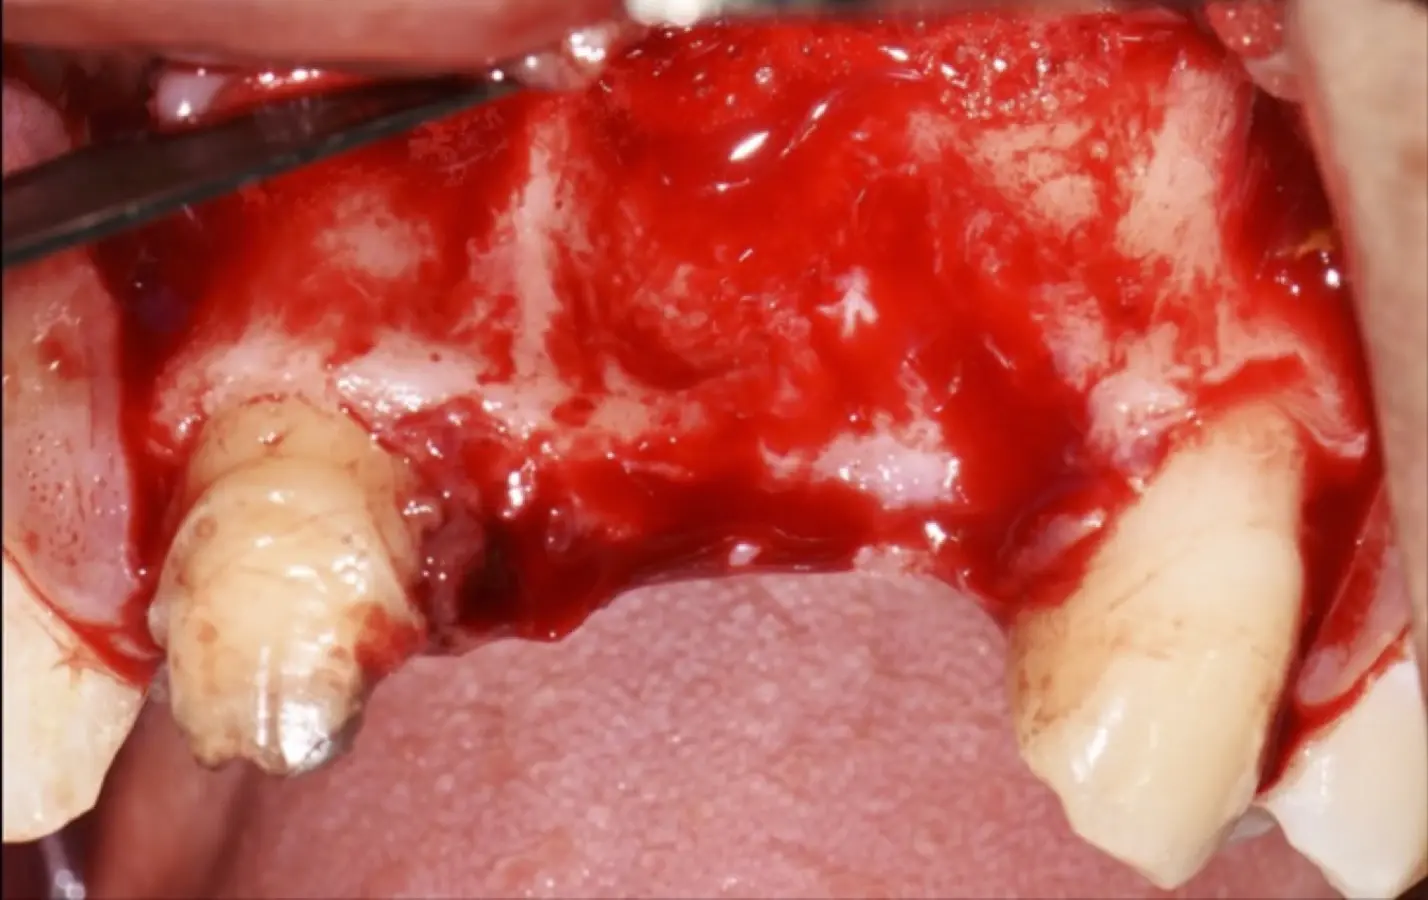

Figura 35. Decolado a espesor total sobrepasando la línea mucogingival (a, b).

Figura 36. Defecto óseo y severa reabsorción ósea horizontal: vista clínica (a) y corte tomográfico (b).

Figura 43. Colocación del biomaterial triturado (a - d).

Figura 44. Pasos para la colocación de la membrana de barrera (a - d).